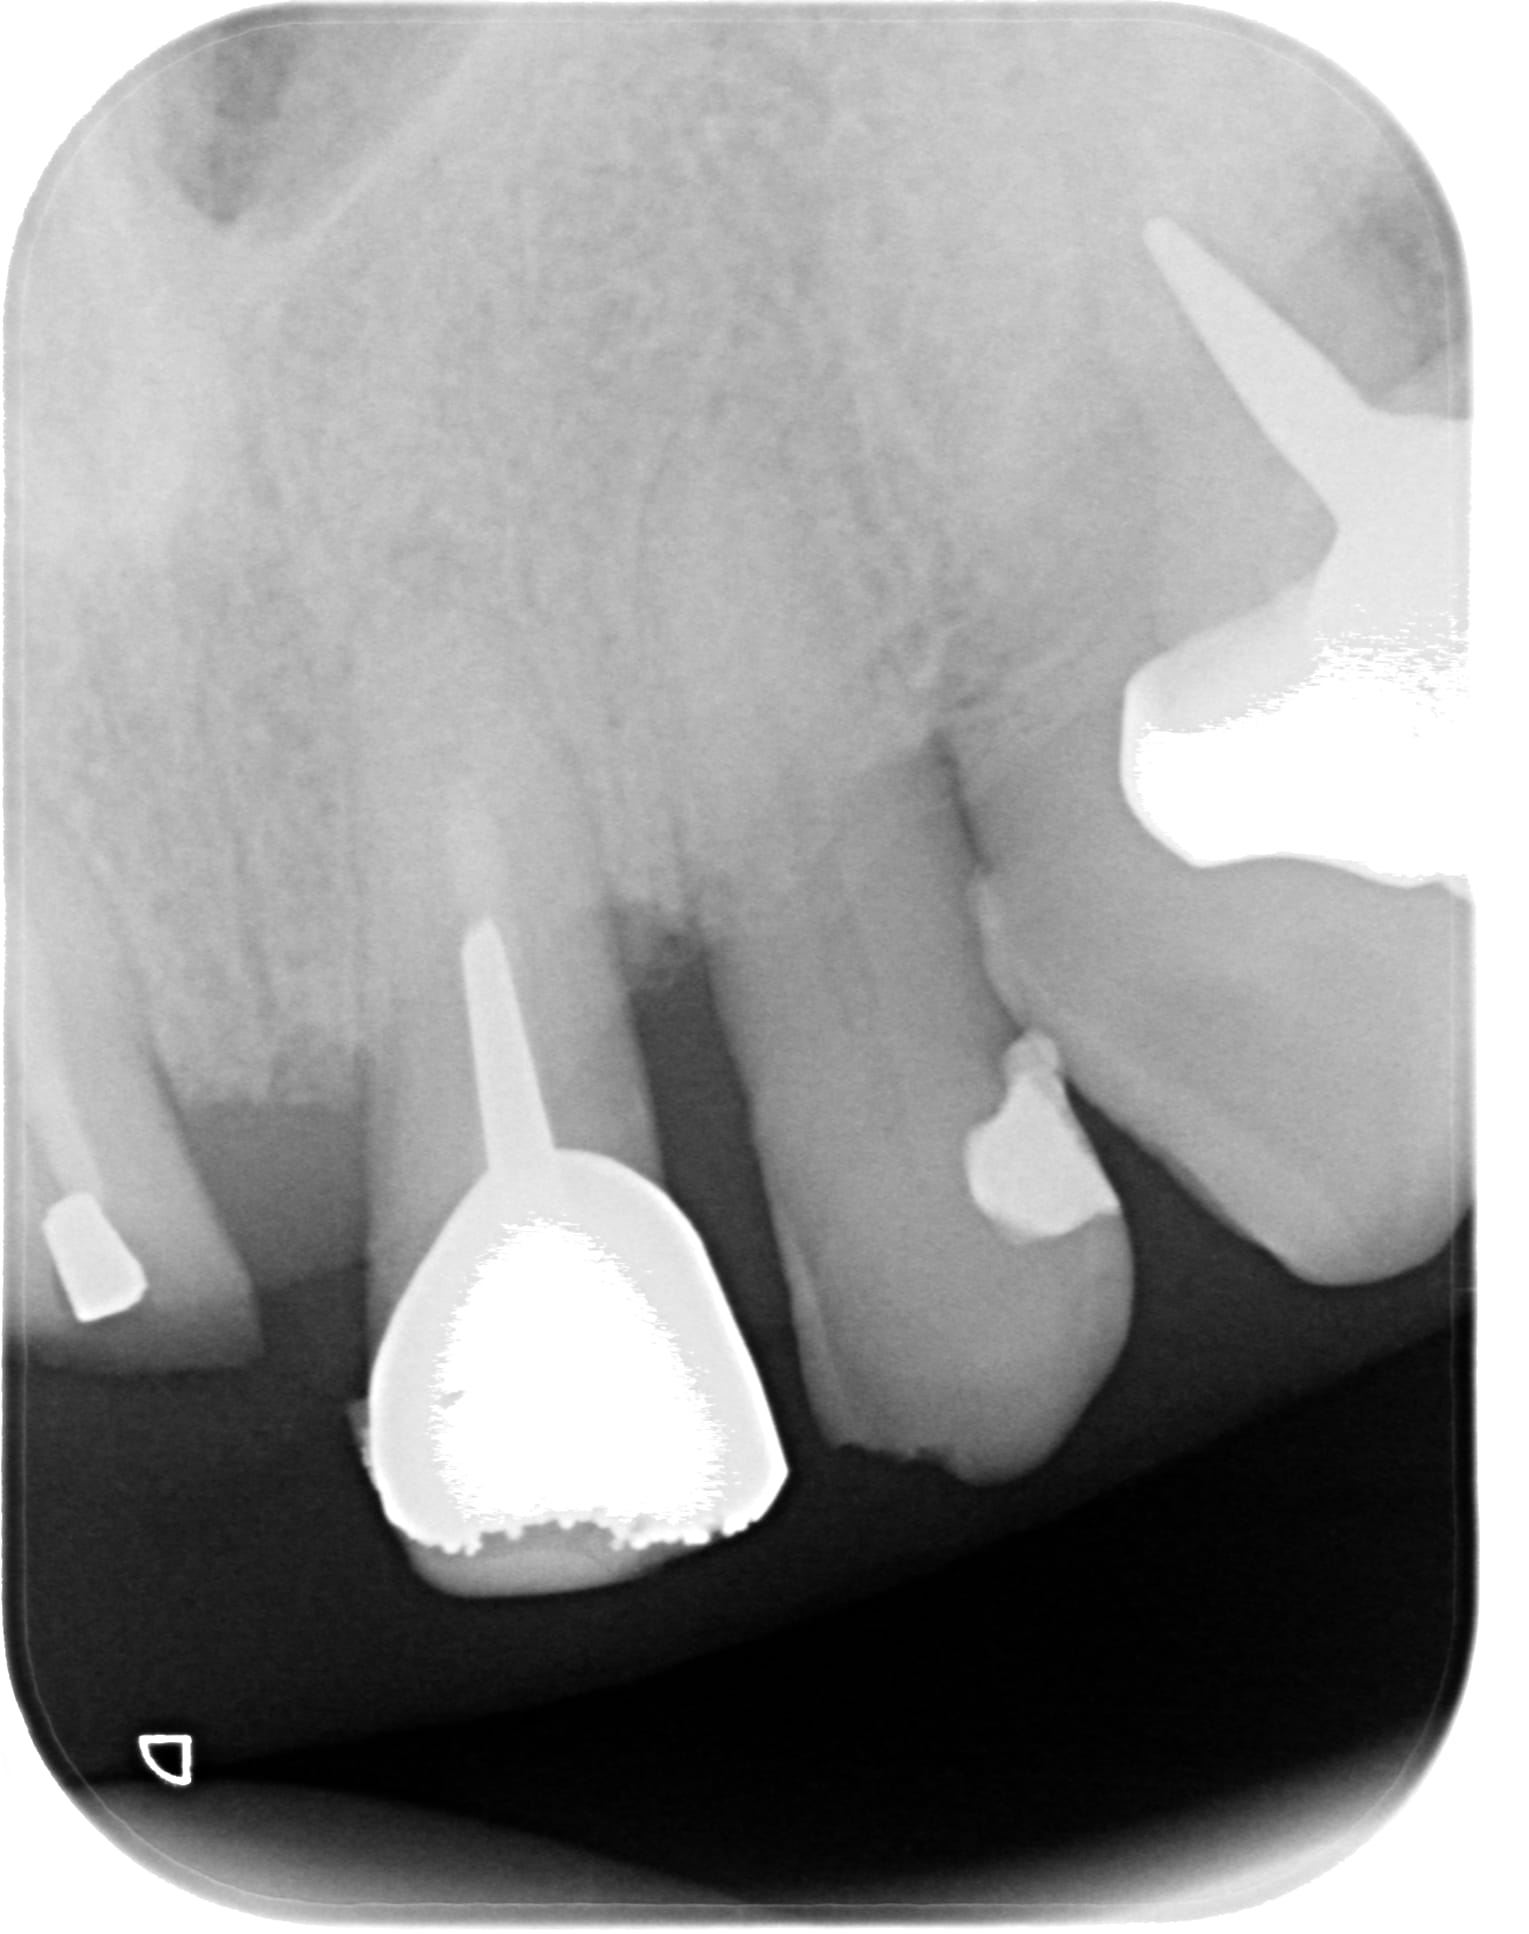

Une motivation au brossage, un det et un surfaçage + tard, histoire de remettre les choses en état, je me retrouve avec ce type de gencive : voir les photos.

Depuis les photos, j'ai viré la couronne de 21 et refait la provisoire, ça va mieux, mais pas tip top pour la gencive.

J'ai passé une fraise à fine granulométrie (bague blanche) pour laisser la racine encore + lisse qu'avec les curettes.

Au sondage on passe les 3 mm quasi partout sur les incisives maxillaires. Ailleurs, de façon générale, ça s'est bien refermé. Pas partout cependant, il doit rester une poche sous une molaire qui s'est versée (de mémoire, j'ai pas son dossier avec moi, juste pris la radio et les photos pour les poster)